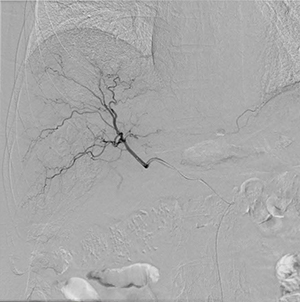

症例2 肝細胞がんに対するTACE

DSA画像:TACEにおける血管造影にて、肝内の細かな末梢血管まで描出が可能 |